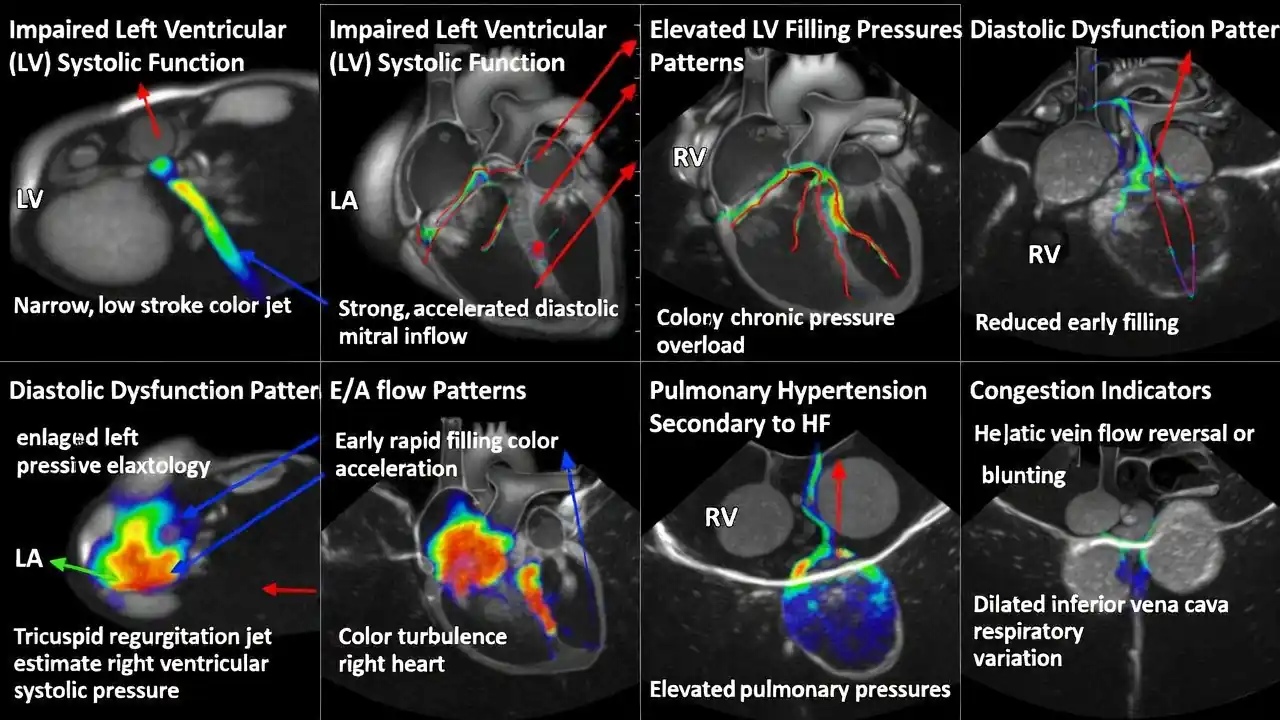

یکی از شایعترین انواع ضربان نامنظم، فیبریلاسیون دهلیزی است که در آن دهلیزها بهطور نامنظم و سریع میتپند. این حالت میتواند خطر لخته شدن خون و سکته مغزی را افزایش دهد. نوع دیگری از آریتمی، PVC یا ضربانهای زودرس بطنی است که معمولاً بیخطرند اما در صورت تکرار زیاد نیاز به بررسی دارند.

برخی آریتمیها باعث ضربان سریع قلب میشوند که به آن تاکیکاردی گفته میشود. این حالت ممکن است با سرگیجه، تنگی نفس یا احساس ضعف همراه باشد. در مقابل، برادیکاردی زمانی رخ میدهد که ضربان قلب بیش از حد کند شود و میتواند باعث خستگی، سنکوپ یا احساس سنگینی در سینه شود.

تشخیص ضربان نامنظم معمولاً با نوار قلب (ECG) آغاز میشود. اگر آریتمی گذرا باشد و در لحظه ثبت نشود، از هولتر ۲۴ تا ۷۲ ساعته یا مانیتورینگ طولانیمدت استفاده میشود. این روشها امکان ثبت ریتم قلب در شرایط واقعی زندگی را فراهم میکنند و برای تشخیص آریتمیهای پنهان بسیار ارزشمندند.

در برخی موارد، پزشک از اکوکاردیوگرافی برای بررسی ساختار قلب و عملکرد دریچهها استفاده میکند. اگر احتمال بیماری عروق کرونر وجود داشته باشد، تست ورزش یا CT آنژیو ممکن است لازم باشد. انتخاب تست مناسب به علائم و شرایط بیمار بستگی دارد.